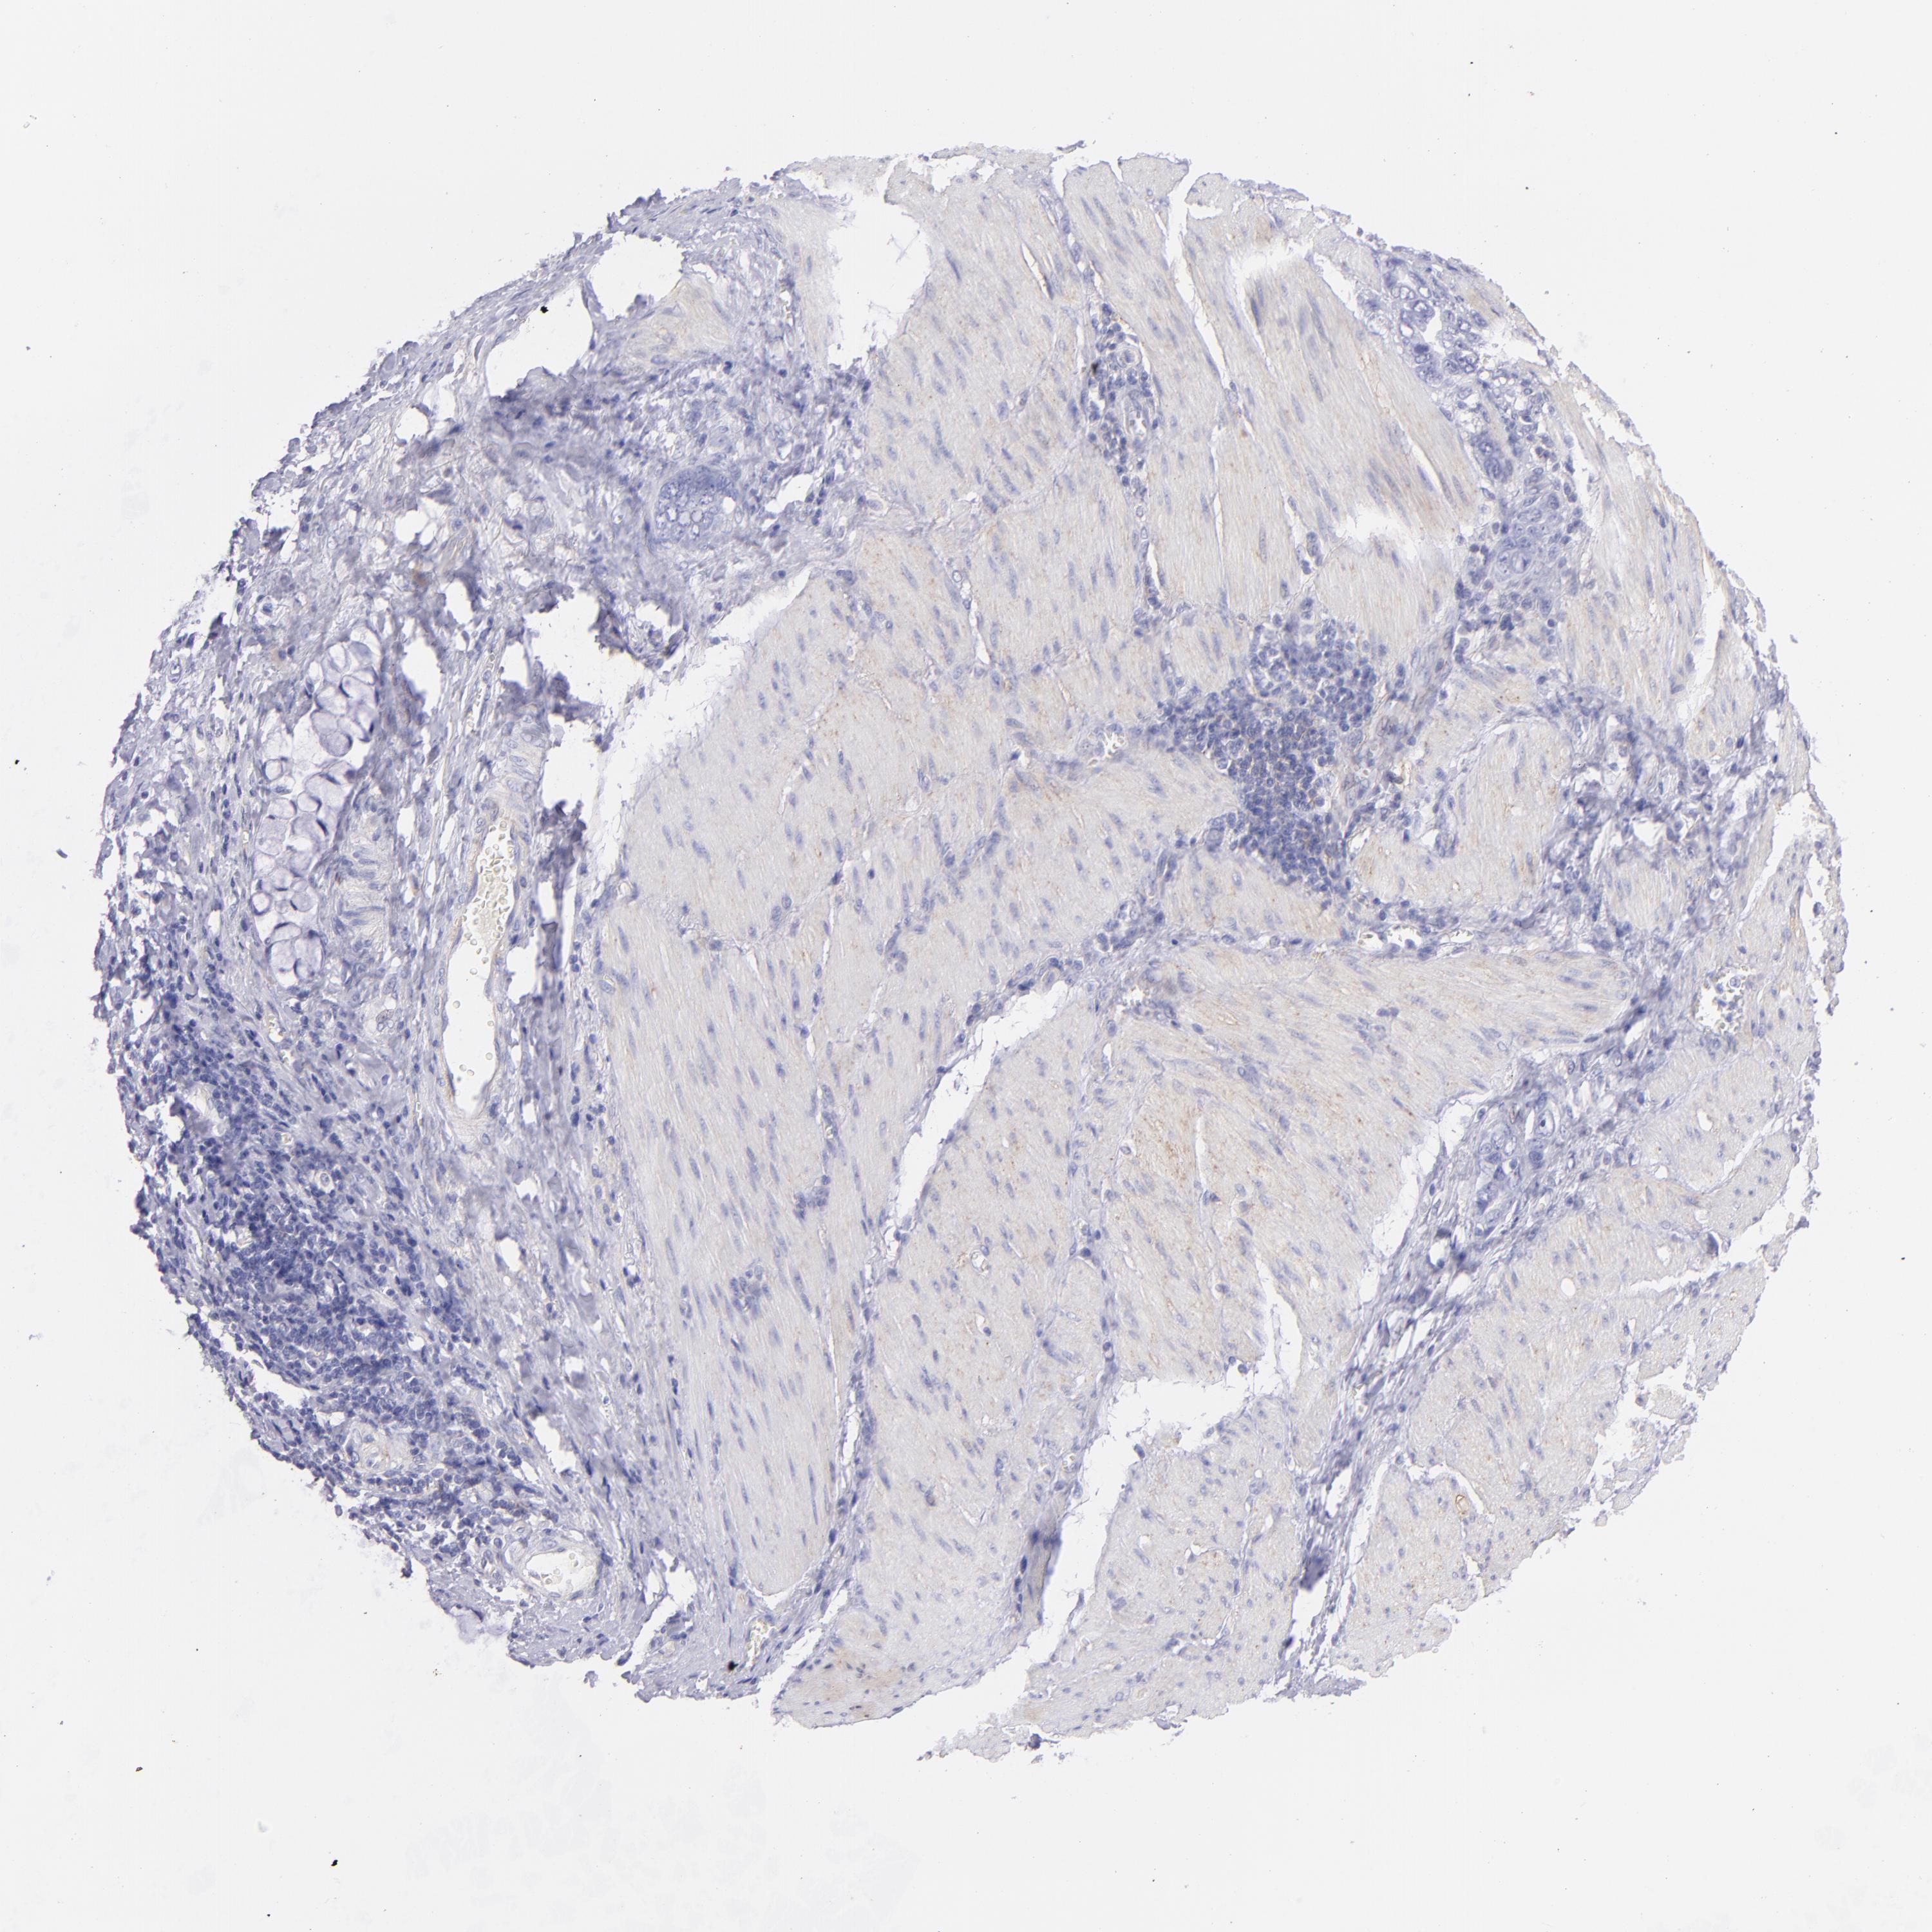

STOMACH CANCER - Protein expressioni

A mouse-over function shows sample information and annotation data. Click on an image to view it in a full screen mode. Samples can be filtered based on level of antibody staining by selecting one or several of the following categories: high, medium, low and not detected. The assay and annotation is described here.

Note that samples used for immunohistochemistry by the Human Protein Atlas do not correspond to samples in the TCGA dataset.

Antibody stainingi

Antibody staining in the annotated cell types in the current human tissue is reported as not detected, low, medium, or high, based on conventional immunohistochemistry profiling in selected tissues. This score is based on the combination of the staining intensity and fraction of stained cells.

Each image is clickable and will lead to virtual microscopy that enables deeper exploration of all samples and also displays staining intensity scores, fraction scores and subcellular localization as well as patient and tissue information for each sample.

Antibody CAB002507

Staining

High

Medium

Low

Not detected

Intensity

Strong

Moderate

Weak

Negative

Quantity

>75%

75%-25%

<25%

None

Location

Nuclear

Cytoplasmic/membranous

Cytoplasmic/membranous,nuclear

Adenocarcinoma, NOS

Adenocarcinoma, High grade